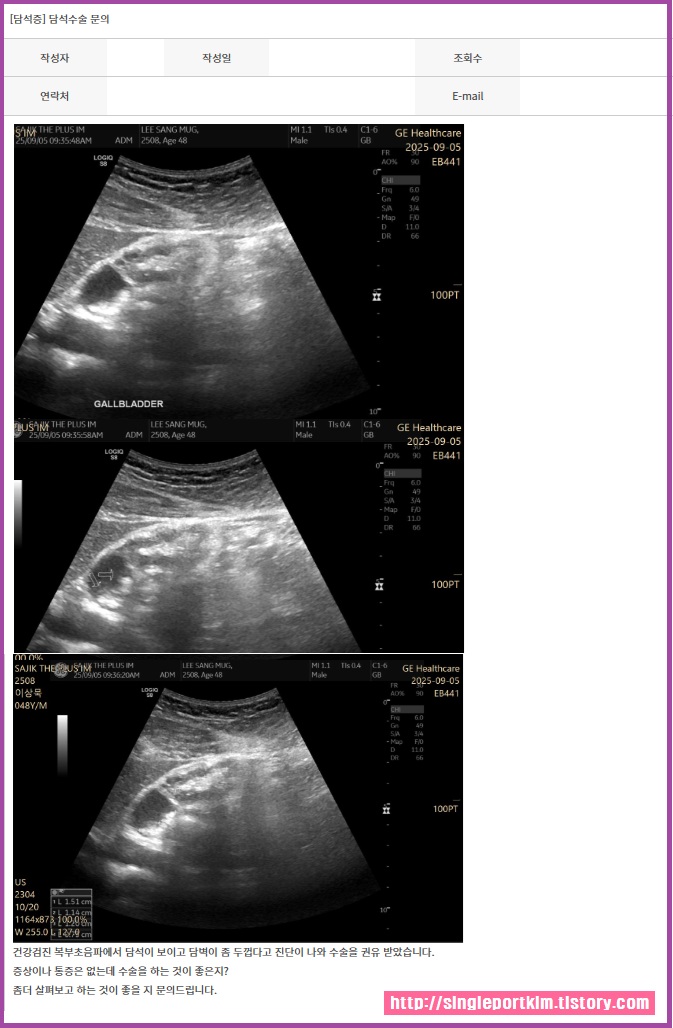

건강검진 복부초음파에서 담석이 보이고 담벽이

좀 두껍다고 진단이 나와 수술을 권유 받았습니다.

환자분 담낭은 현재 4/5가 망가져서 기능이 없는 장기 입니다.

통증은 1/5 부분 때문에 없습니다.